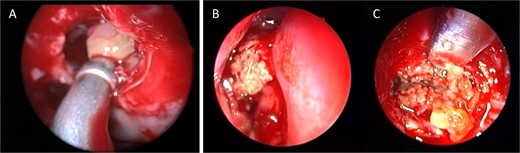

A 37-year-old female with a history of bronchial asthma, complained mainly of chronic headache, left sided facial pain, which was associated with persistent post-nasal drip. Endoscopic examination showed left-sided tenacious discharge filling the middle meatus with grade two polyps. NCCT (Fig. 5) showed left isolated heterogenous maxillary sinus opacity suggestive of allergic fungal sinusitis. She underwent endoscopic sinus surgery (Fig. 6) with removal of fungal mucin and mud, complete left maxillary sinus aeration was ensured. The patient was free of symptoms during her 1 week follow up.

Intra-operative endoscopic view showing (A) polyps in the left osteomeatal complex with (B and C) fungal mud and mucin.